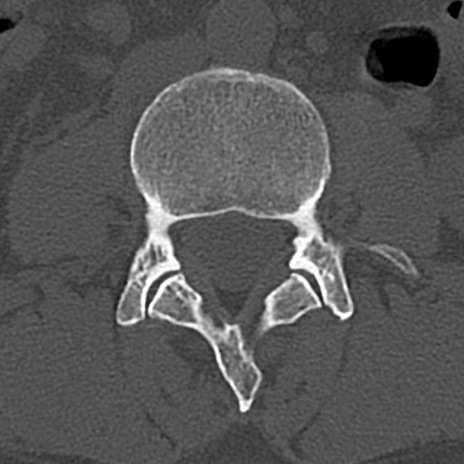

【整形】TIPS症例4 腰椎CT(横断像)

腰椎CT

横断像と矢状断像